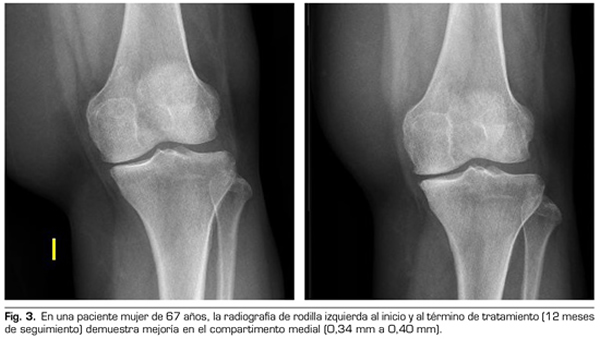

9.	Fernández-Cuadros ME, Pérez-Moro OS, Albaladejo-Florín MJ. Knee osteoarthritis: Condroprotector action and symptomatic effect of ozone on pain, function, quality of life, minimal joint space and knee arthroplasty delay. Middle East J Rehabil Health Stud. 2017;4(1):e43200. DOI: 10.17795/mejrh-43200.